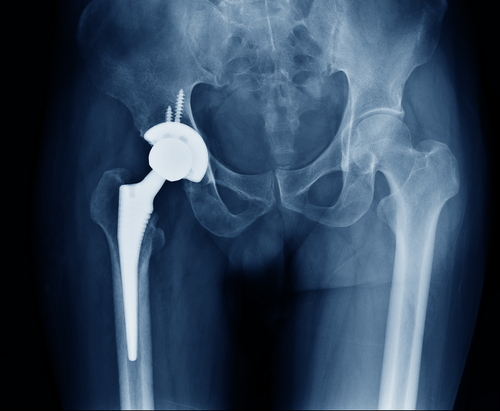

One medical device company that has been in the headlines for its substantial number of recalls is Exactech. Exactech is a global medical device company that is responsible for producing joint replacement devices. Within the past two years, the company has had to issue two recalls regarding knee, hip, and ankle replacements.

The first recall occurred in the summer of 2021 when a design defect was discovered in a hip liner model that is commonly attached to a hip replacement system. The defect led to a recall of nearly 90,000 hip replacement devices due to early device failure and premature wear. The second recall occurred in February of this year and occurred because there was a defect discovered in the knee replacement devices.

Ever since both recalls have been issued, surgeons have been advised to stop installing all Exactech knee, hip, and ankle replacements in patients. Manufacturers are required to return all defective devices to the company. Patients who already have a recalled Exactech device inside of their body should contact their healthcare provider immediately for an evaluation. Healthcare providers are advised to keep a list of patients with recalled Exactech devices and monitor their progress for signs of device failure.

Patients with recalled Exactech devices may experience symptoms like swelling, instability in the affected joint area, bone loss, an inability to place weight on the affected area, and overall decreased mobility. When patients are experiencing these types of symptoms, healthcare providers may conduct an X-ray to study the status of the recalled device.

Depending on the results, the healthcare provider may recommend corrective surgery to remove the recalled device. For patients who do not experience these types of symptoms, corrective surgery may not be recommended. The decision to conduct corrective surgery will be determined by the healthcare provider and the patient.